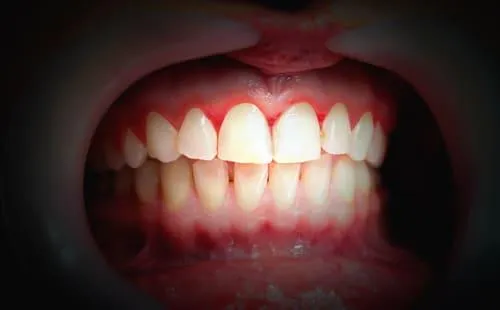

Przerost dziąseł jak wygląda? To pytanie zadaje sobie wiele osób, które zauważają zmiany w wyglądzie dziąseł. Charakterystycznym objawem jest nadmierny rozrost tkanki dziąseł, która może częściowo lub całkowicie przykrywać zęby. Może to prowadzić do trudności w utrzymaniu higieny, a także do nieestetycznego wyglądu uśmiechu.

| Różowy kolor, gładka powierzchnia | Czerwony lub ciemnoczerwony kolor, nierówna powierzchnia |

| Dziąsła przylegają ściśle do zębów | Dziąsła odstają od zębów, tworząc kieszonki |

| Brak krwawienia podczas szczotkowania | Częste krwawienie i ból |